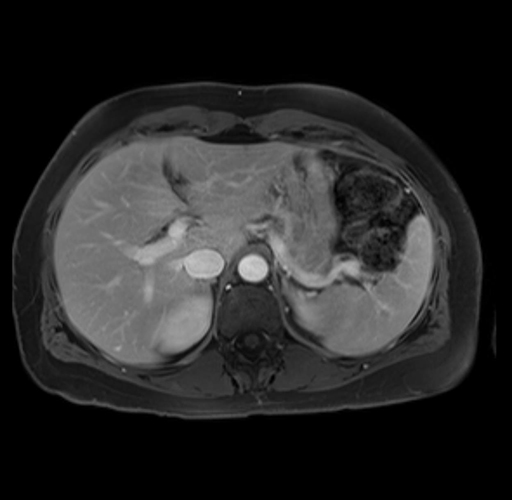

Imaging Analysis

Look through the patient's CT scan to identify any areas of concern for the necessary procedure.

Based on your CT findings, which issue(s) are present and would give reason for "planned slowing down moment(s)" in this case?

Considering a standard distal pancreatectomy procedure, what step(s) of the operation would you do differently in this case?